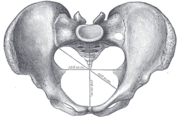

Diameters of pelvic inlet

A distinction is made between the lesser or true pelvis inferior to the terminal line, and the greater or false pelvis above it. The pelvic inlet or superior pelvic aperture, which leads into the lesser pelvis, is bordered by the promontory, the arcuate line of ilium, the iliopubic eminence, the pecten of the pubis, and the upper part of the pubic symphysis. The pelvic outlet or inferior pelvic aperture is the region between the subpubic angle or pubic arch, the ischial tuberosities and the coccyx. [2]

Alternatively, the pelvis is divided into three planes: the inlet, midplane, and outlet.[3]